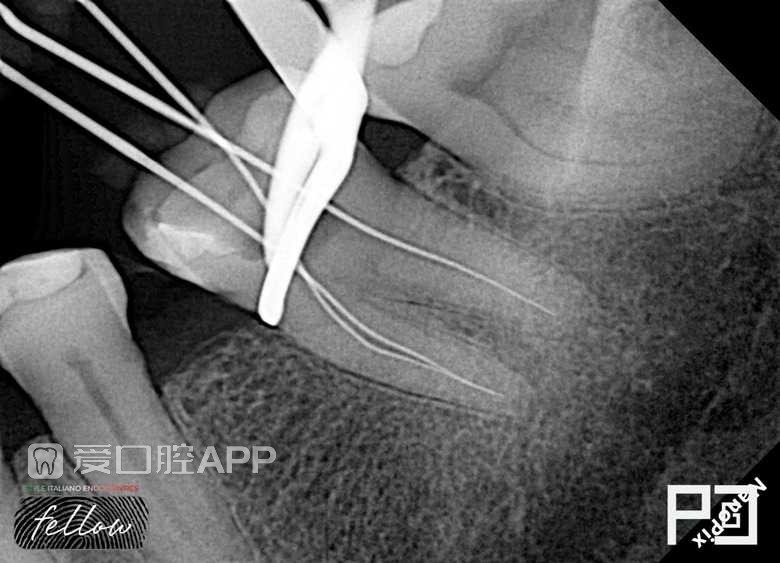

看个根充 —— 下颌第一磨牙

by Paco CG